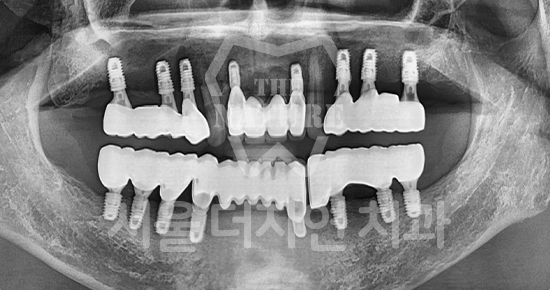

#Full Mouth Implants

-

BEFORE: 2022.12.15

AFTER: 2023.02.23